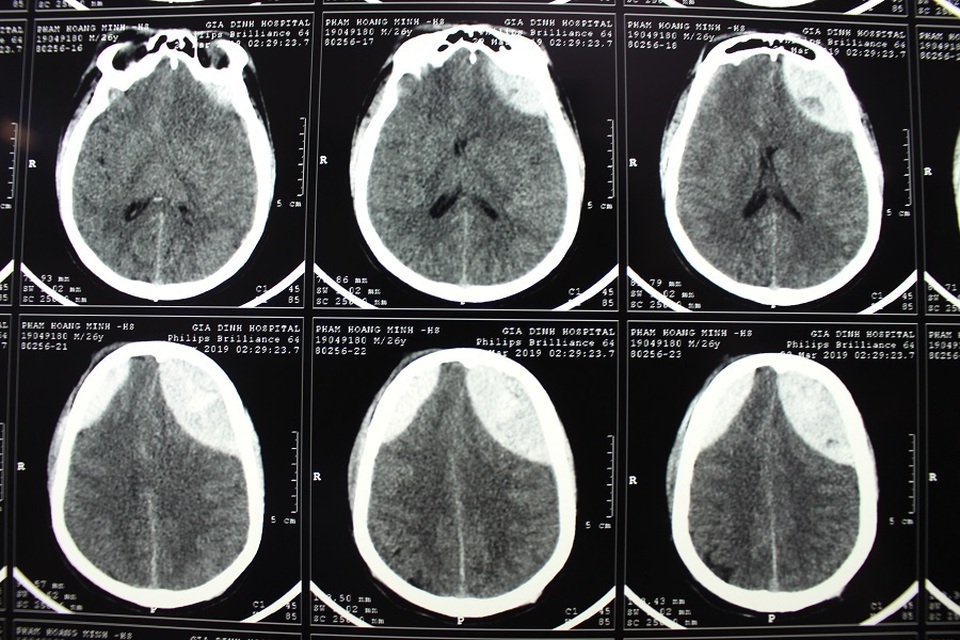

Máu tụ bán cầu não 2 bên đỉnh trán (vùng trắng) trên phim khiến Minh nguy kịch

Các bác sĩ đã phẫu thuật mở hộp sọ lấy máu tụ cho Hoàng Minh

BS Nguyễn Trung Cường, khoa Hồi sức Ngoại, Bệnh viện Nhân Dân Gia Định cho hay: Bệnh nhân bị chấn thương sọ não, có máu tụ ngoài màng cứng vùng trán đỉnh 2 bên, sau nhập viện khối máu gia tăng, tri giác giảm nên được chỉ định phẫu thuật. Tuy nhiên, khi chỉ định mổ thì gia đình không lo nổi viện phí. Xác định bệnh nhân đang rơi vào nguy hiểm, bệnh viện quyết định thực hiện phẫu thuật mở hộp sọ lấy máu tụ. Sau 6 ngày hồi sức, bệnh nhân đã cai được máy thở, sinh hiệu dần ổn định, chuyển lên khoa Ngoại Thần kinh. Đây là ca chấn thương nặng, chúng tôi cần phải tiếp tục theo dõi, điều trị để hạn chế những di chứng cho người bệnh.